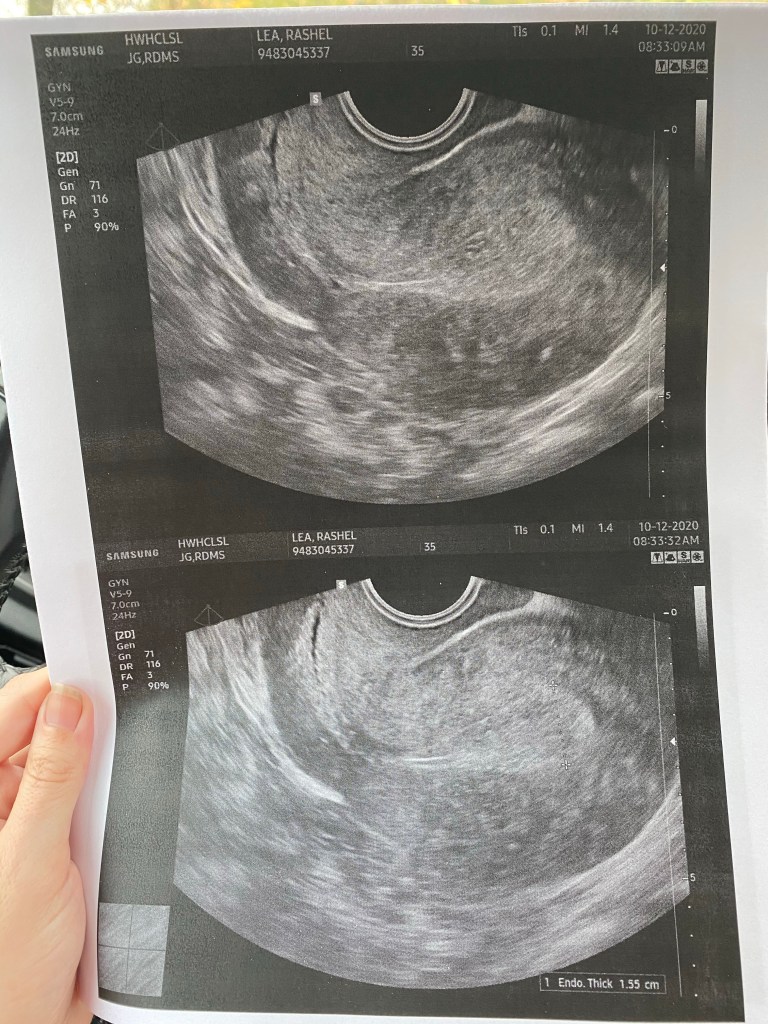

Well last week we had some changes thrown at us. They decided that my transfer would be moved from the 16th to the 19th! So a bit of a bummer but all should be fine. Today I had another ultrasound and blood work appointment. My lining looks soooo good 15 now! I feel much better about this thick lining.